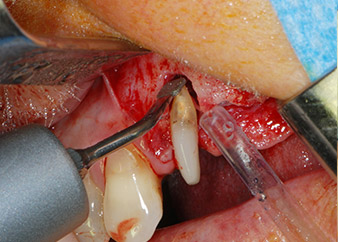

However, we maintained our initial plan to retain both teeth as temporary bridge abutments during the six-months osseointegration period of the implants. At reentry, the situation would have to be reassessed. First, in an attempt to manage the endo-perio problem, the remaining root surface was carefully debrided with piezoelectric equipment (Piezomed, W&H, used with the spatula-shaped insert S1, originally designed for erosion of the lateral sinus wall) (Fig. 4).

Then the apex was abraded with the same instrument to remove residual infected apical tissue and to reduce possible accessory root-canal ramifications (apicoectomy) (Fig. 5). A retrograde filling was not necessary because the orthograde filling had just been revised.